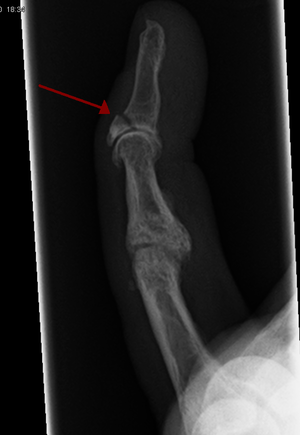

Mallet finger

- Rupture of extensor tendon in area of distal phalanx distal to DIP joint

- May be accompanied by avulsion fracture

- Caused by forced flexion of the DIP joint

- Finger x-ray (PA and lateral)

The injured digit will be often held in flexion with an inability to extend. The diagnosis is clinical although an avulsion fracture should also be ruled out.